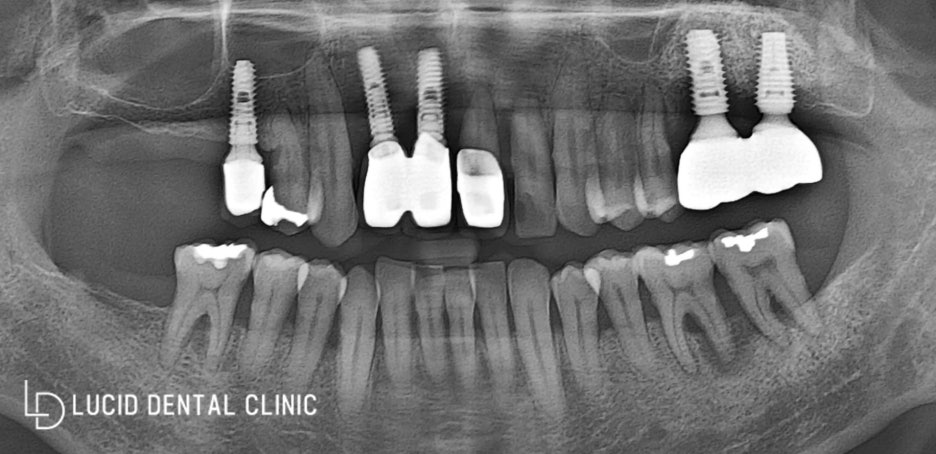

사진을 보게 되면

이전에 이미 임플란트를

많이 식립하고 나서 내원하셨는데요

나사 볼트처럼 보이는 걸

'픽스처'라 하는데, 이것이 잇몸뼈조직에

단단히 잘 유착이 되어야 됩니다.

환자의 파노라마 사진을 다시 보시면

문제가 있는 곳이 여러 군데 있습니다.

- 첫 번째 위쪽 앞니 (전치)

전치에 보철이 되어 있는데요.

뼛속에 박혀있던 픽스처가 골 소실과 감염으로 인해

뼈가 단단히 잡아주지 못해, 흔들리고 있었습니다.

- 두 번째 위에서 좌측 (소구치)

환자께서 통증이 있다고

말씀하기도 했고 뿌리도 내려와

동요(흔들림)가 나타나고 있었는데요.

- 세 번째 위 오른쪽 어금니 (대구치)

사진을 보면 아실 수 있는 것처럼

현재 구치부 치아가 없었습니다.

사진을 보시면 픽스처가

단단히 뼈에 잘 유착이 돼야 되는데

검하고 둥그런 부위가 관찰이 되고 있습니다.

이것을 '상악동'이라 부르는데,

- 하악 좌측 어금니 (대구치)

대구치 2개 전부 골 소실로 인해

흔들리고 통증이 있다고 말씀하셨습니다.

- 하악 우측 어금니 (대구치)

대구치 한 개가 없으시기 때문에

자 이제 우리 논현동 치과에서

치아 상태가 안 좋았던 것들에 대한

모든 진료 계획을 실행해서

완성한 파노라마 x-ray 사진이에요.

진단하기 전 파노라마 x-ray와 달리

현재 구강 내 모든 면이 골고루

사용할 수 있게 완성이 됐습니다.

엑스레이로 확인해 보니,

단단하게 식립이 잘 되었고

성공적으로 치료되었네요 :)